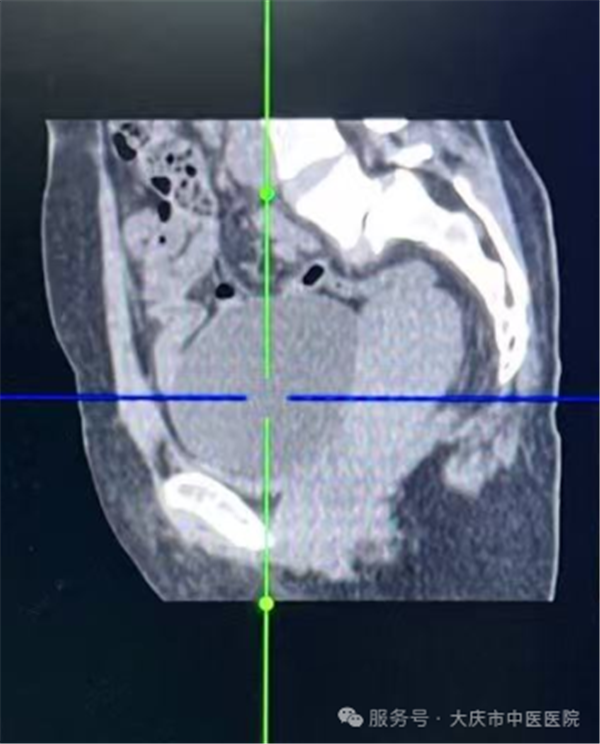

这项技术的核心优势在于“精准微创”,手术全程在超声实时监控下开展,医生通过细针经皮肤穿刺进入囊肿内部,先将囊液彻底抽出,再向囊内注入硬化剂,破坏囊肿内壁的分泌细胞,有助于降低复发风险。整个操作无需切开腹部,创伤仅为针尖大小,对周围组织影响极小。

从临床操作来看,这类手术流程规范,医护团队会严格执行无菌操作,全程监控穿刺路径与针尖位置,确保每一步操作精准可控。由于创伤极小,患者术中多无明显腹部不适感,出血量极少,整台手术耗时通常不足30分钟,能最大程度减少对正常生活工作的干扰。